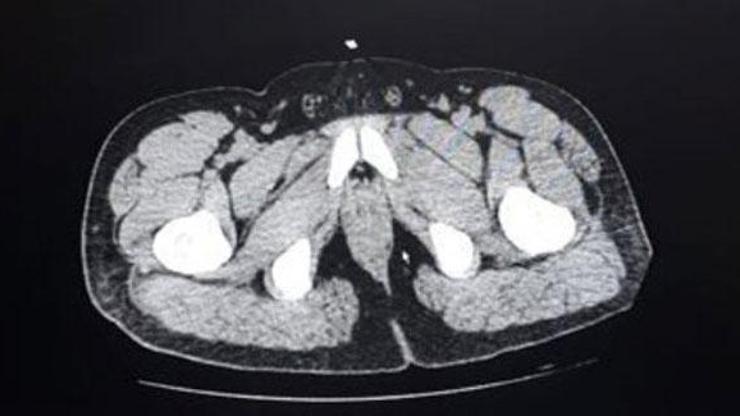

İl Emniyet Müdürlüğü Narkotik Suçlarla Mücadele Şube Müdürlüğü ekipleri, yabancı uyruklu bazı şüphelilerin 'yutma yöntemiyle' kente uyuşturucu getireceğini öğrendi. İran uyruklu F.D.ve V.D. adlı zanlıları tespit ederek takibe alan ekipler, şüphelileri Denizli Otobüs Terminali'nde yakalayarak gözaltına aldı. Denizli Devlet Hastanesi'ne götürülen zanlıların, uzman personel tarafından yapılan kontrollerinde, mide ve bağırsak kısımlarında yabancı madde olduğu tespit edildi. Şüphelilerden F.D'nin 65 paket halinde 588 gram, V.D'nin ise 35 paket halinde 317 gram metamfetamini yuttuğu belirlendi. Polis kontrolünde doğal yollardan çıkarılan 100 paket halinde 905 gram metamfetamin maddesine el konuldu. Adliyeye sevk edilen 2 şüpheli, sevk edildiği adliyede tutuklandı.